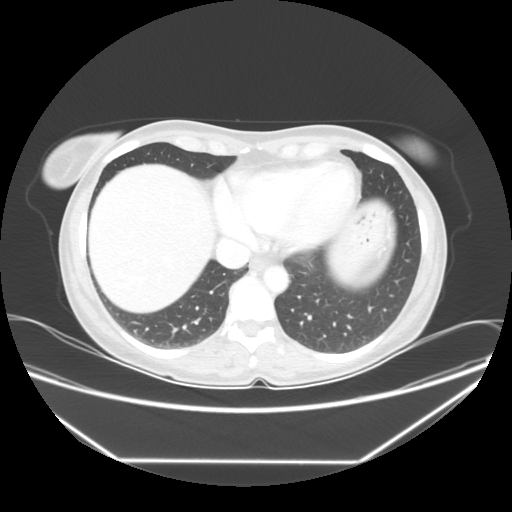

Image Grid

4Γ—3 grid: Rows show different image types (Original NATIVE, Reconstructed NATIVE, Original VENOUS, Generated VENOUS), Columns show windowing techniques (No Window, Lung Window, Mediastinum Window)

Original NATIVE CT scan (input)

Full window (WL 1023.5, WW 4095 β†’ Low βˆ’1024, High +3071)

Generated VENOUS CT scan (A→B translation)